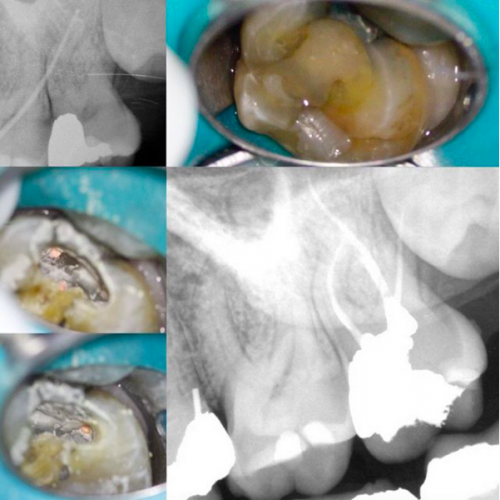

Cracked tooth

By Revathi Miglani / July 13, 2018

54 yr old male reported with pain and temperature sensitivity in relation to #18 for […]